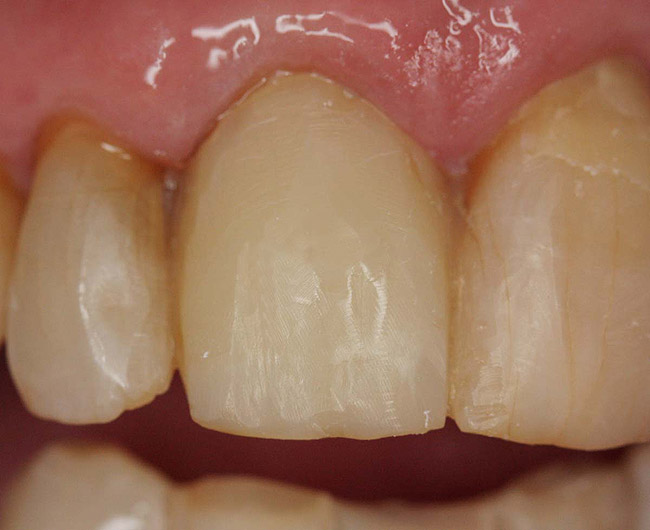

Figure 12  Endodontically treated mandibular central incisors that require only restoration of endodontic access holes with composite.

Figure 12

Figure 13  Access holes after endodontic treatment.

Figure 13

Figure 14  Final restoration with bonded composite.

Figure 14

Class IC mandibular central incisors had extensive amounts of tooth structure remaining following endodontic treatment (Figure 12 and Figure 13). Restoration of the access holes was completed with bonded composite (Figure 14).